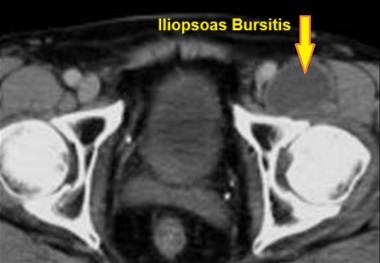

Iliopsoas bursitis is a painful type of hip bursitis caused by irritation and inflammation of the iliopsoas bursa.

The iliopsoas bursa is a small fluid-filled sac located between one of the hip muscles (iliopsoas) and the front part of the hip joint.